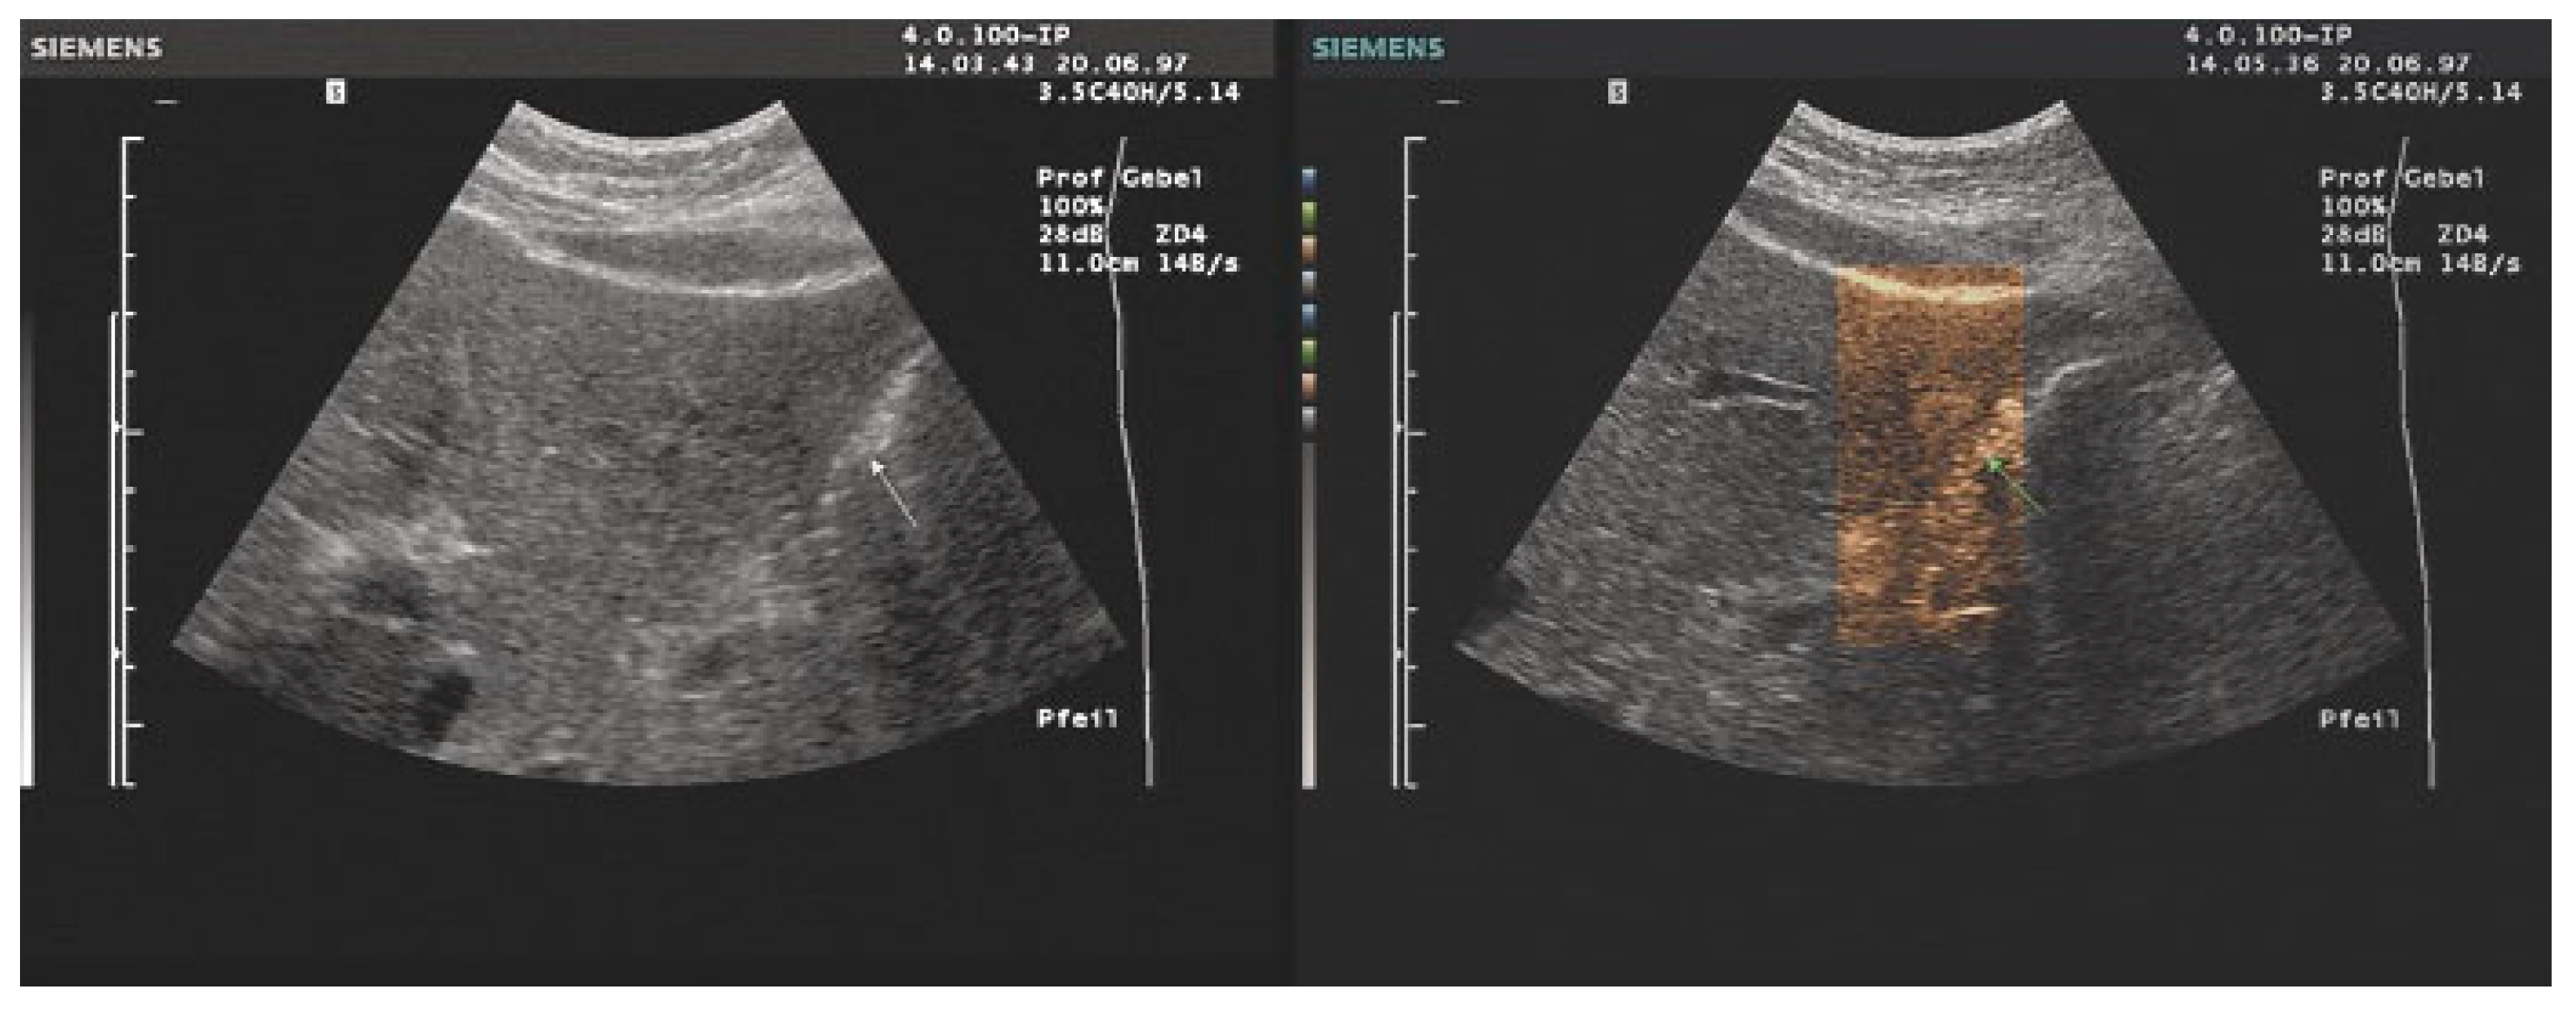

- The combination with speckle filters available in all high-end devices, similar to the low-pass filters used by Bleck et al. (1994) for tissue visualization [5], also yields significantly improved visualization results (Figure 5, Figure 6 and Figure 7). In principle, applications with new visualized texture analyses, such as random field models, are also conceivable [76,77].

- Fischer, T.; Filimonow, S.; Taupitz, M.; Petersein, J.; Beyersdorff, D.; Bollow, M.; Hamm, B. [Image quality and detection of pathology by ultrasound: Comparison of B-mode ultrasound with photopic imaging and tissue harmonic imaging alone and in combination]. Rofo 2002, 174, 1313–1317. [Google Scholar] [CrossRef] [PubMed]

- Merkel, D.; Brinkmann, E.; Kammer, J.C.; Kohler, M.; Wiens, D.; Derwahl, K.M. Comparison Between Various Color Spectra and Conventional Grayscale Imaging for Detection of Parenchymal Liver Lesions With B-Mode Sonography. J. Ultrasound Med. Off. J. Am. Inst. Ultrasound Med. 2015, 34, 1529–1534. [Google Scholar] [CrossRef]